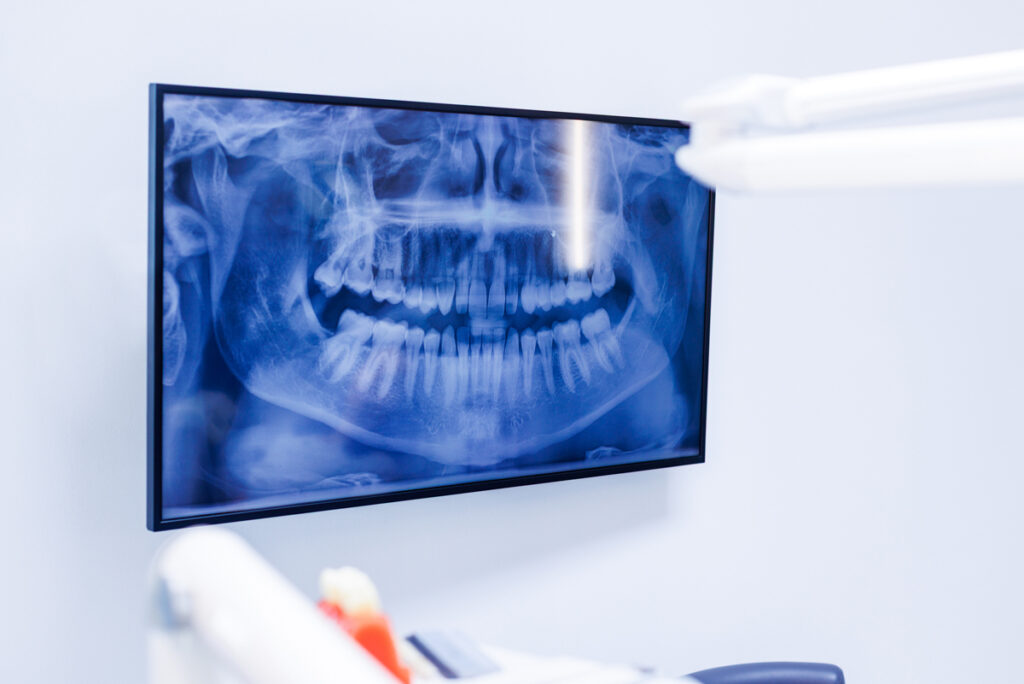

Diagnosztika – legyen meg a pontos kép

A pontos tervezéshez sok esetben 3D CT (CBCT) felvételre is szükség van, mert ebből látszik igazán a csonthelyzet és az anatómia. Ha van friss CT felvétel, érdemes elhozni vagy előre elküldeni, és abból dolgozunk.

Ha nincs, nálunk helyben is elérhető a vizsgálat, külön díj ellenében. Így jellemzően nincs sorban állás és nincs felesleges plusz alkalom csak a képalkotás miatt, ami a legtöbb páciensnek kényelmi és időbeli előny.

A precíz tervezéshez sok esetben 3D CT (CBCT) felvételre is szükség van. Ha van friss CT, érdemes elhozni. Ha nincs, nálunk helyben is el tudjuk készíteni, külön díj ellenében, és erről előre, egyértelműen tájékoztatjuk. Ennek a gyakorlati előnye az, hogy nem kell külön helyre menni, és nem kell felesleges plusz alkalmakat szervezni csak a képalkotás miatt.

Alapos állapotfelmérés és diagnosztika alapján. A legbiztosabb válasz akkor adható meg, ha a szájsebészeti vizsgálat mellett rendelkezésre áll a megfelelő képalkotás is – a legtöbb esetben egy 3D CT (CBCT) felvétel. Ez segít pontosan megítélni a csontmennyiséget, a csontminőséget és az anatómiai viszonyokat, így nem találgatásból születik döntés. A végső választ egy tételes kezelési terv adja meg, mert abból egyértelműen látszik, mi szükséges az adott esetben, mi nem, és milyen lépések mentén tervezhető a folyamat.

Csontpótlás akkor jön szóba, ha a hiányzó fog helyén a csont mennyisége vagy formája nem ad elég stabil alapot az implantátumnak. Ez jelentheti azt, hogy a csont nem elég magas, nem elég széles, vagy az adott területen a csontminőség nem ideális a biztonságos rögzüléshez. Hogy az Ön esetében valóban szükség van-e csontpótlásra, és pontosan milyen megoldás a legkiszámíthatóbb, azt vizsgálat után lehet felelősen megmondani – gyakran 3D CT (CBCT) felvétel alapján, mert ezen látszik a csont állapota és az anatómiai adottságok is.